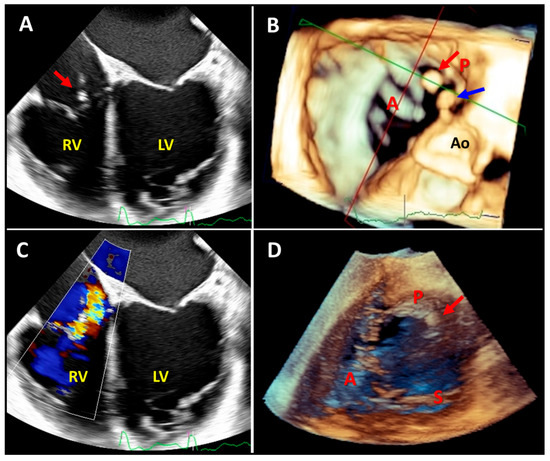

- Badano, L.P.; Hahn, R.; Rodríguez-Zanella, H.; Araiza Garaygordobil, D.; Ochoa-Jimenez, R.C.; Muraru, D. Morphological Assessment of the Tricuspid Apparatus and Grading Regurgitation Severity in Patients with Functional Tricuspid Regurgitation: Thinking Outside the Box. JACC Cardiovasc. Imaging 2019, 12, 652–664. [Google Scholar] [CrossRef] [PubMed]

- Addetia, K.; Muraru, D.; Veronesi, F.; Jenei, C.; Cavalli, G.; Besser, S.A.; Mor-Avi, V.; Lang, R.M.; Badano, L.P. 3-Dimensional Echocardiographic Analysis of the Tricuspid Annulus Provides New Insights into Tricuspid Valve Geometry and Dynamics. JACC Cardiovasc. Imaging 2019, 12, 401–412. [Google Scholar] [CrossRef]

- Badano, L.P.; Caravita, S.; Rella, V.; Guida, V.; Parati, G.; Muraru, D. The Added Value of 3-Dimensional Echocardiography to Understand the Pathophysiology of Functional Tricuspid Regurgitation. JACC Cardiovasc. Imaging 2021, 14, 683–689. [Google Scholar] [CrossRef]

- Muraru, D.; Gavazzoni, M.; Heilbron, F.; Mihalcea, D.J.; Guta, A.C.; Radu, N.; Muscogiuri, G.; Tomaselli, M.; Sironi, S.; Parati, G.; et al. Reference ranges of tricuspid annulus geometry in healthy adults using a dedicated three-dimensional echocardiography software package. Front. Cardiovasc. Med. 2022, 9, 1011931. [Google Scholar] [CrossRef] [PubMed]

- Velayudhan, D.E.; Brown, T.M.; Nanda, N.C.; Patel, V.; Miller, A.P.; Mehmood, F.; Rajdev, S.; Fang, L.; Frans, E.E.; Vengala, S.; et al. Quantification of tricuspid regurgitation by live three-dimensional transthoracic echocardiographic measurements of vena contracta area. Echocardiography 2006, 23, 793–800. [Google Scholar] [CrossRef] [PubMed]

- Chen, T.E.; Kwon, S.H.; Enriquez-Sarano, M.; Wong, B.F.; Mankad, S.V. Three-dimensional color Doppler echocardiographic quantification of tricuspid regurgitation orifice area: Comparison with conventional two-dimensional measures. J. Am. Soc. Echocardiogr. 2013, 26, 1143–1152. [Google Scholar] [CrossRef]

- Song, J.M.; Jang, M.K.; Choi, Y.S.; Kim, Y.J.; Min, S.Y.; Kim, D.H.; Kang, D.H.; Song, J.K. The vena contracta in functional tricuspid regurgitation: A real-time three-dimensional color Doppler echocardiography study. J. Am. Soc. Echocardiogr. 2011, 24, 663–670. [Google Scholar] [CrossRef]